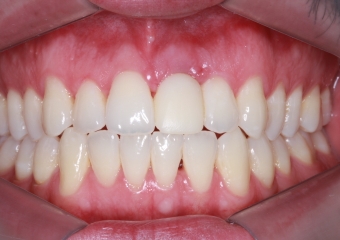

Foto Frontal Inicial 18-05-15